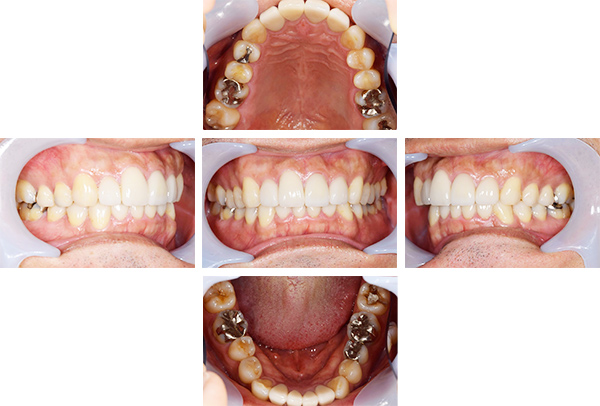

歯列矯正・インレー・クラウン症例

前歯が黒っぽいのが気になる、

悪いところは全部治したい

年齢 54代女性

主訴 歯をきれいにしたい

治療

期間

4年

費用 セラミックインレー 12本

660,000円

オールセラミックプレミアムクラウン 3本

495,000円

矯正 874,900円

計 2,029,900円(税込)

※全て税込となります。

症例写真(治療前)

担当医師所見

治療前:

八重歯が目立ちます。また銀歯もおおく、見た目が気になります。虫歯も散見できます。

レントゲン写真(治療前)

根の治療を3本すでに治療されています。1本根の奥の詰め物が疎になっていますので、根の部分の再治療も行う必要がありそうです。銀歯の中で虫歯になっているものもあります。

治療中

矯正装置をつけています。だんだん八重歯が動いてきているのがわかります。今回のケースでは、抜歯を行わずに矯正ができました。

症例写真(治療後)

治療後:

矯正治療と虫歯の治療すべて終わったときの写真になります。見た目も最初の頃とは全く違いますし、お口の中もすごく綺麗です。

方針

まずは虫歯の治療を行い、被せ物をする部分は仮歯をいれて矯正を行う。矯正終了後、仮歯の部分を最終的な被せ物に変えていく。また気になっていた銀歯もセラミックに変えて終了となった。

内容

セラミックインレー、オールセラミックプレミアム、矯正

特記

事項

虫歯の治療によって歯が一時的に染みるようになる可能性があります。また、歯を抜かずに矯正を行っていますが、全ての方で歯を抜かずに矯正ができるわけではありません。

治療リスク・副作用

・詰め物を銀歯からセラミック等のインレーに変えると、歯がしみることがある

・被せ物をやりかえる時は中で大きく虫歯になっていたり、歯が割れている場合は抜歯になることもある

・インプラント治療は骨と結合するのに期間がかかるが、個人差がある

・ホワイトニング後は歯がしみることがある

・詰め物、被せ物をする時は自分の歯を削ることになります